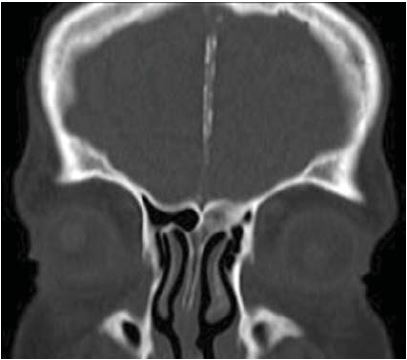

La tomografía helicoidal multicorte revela calcificación de la hoz del cerebro (figura 4), costilla bífida (figura 5). A nivel de los maxilares se observa imagen isodensa localizada en maxilar superior derecho, de forma ovalada, bordes definidos y corticalizados, presentando el adelgazamiento de la cortical ósea vestibular. Descripción imagenológica compatible con QQO (figura 6).